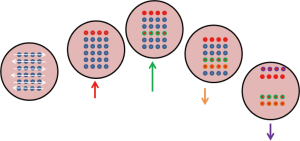

As shown in Figure 7, the target is simulated to move diagonally in a periodic manner, while a particle beam sweeps across left to right and top to bottom. Some parts of the tumour get irradiated only when it crosses the path of the sweeping pencil beam. This will result in regions of over-dose and under-dose (20).